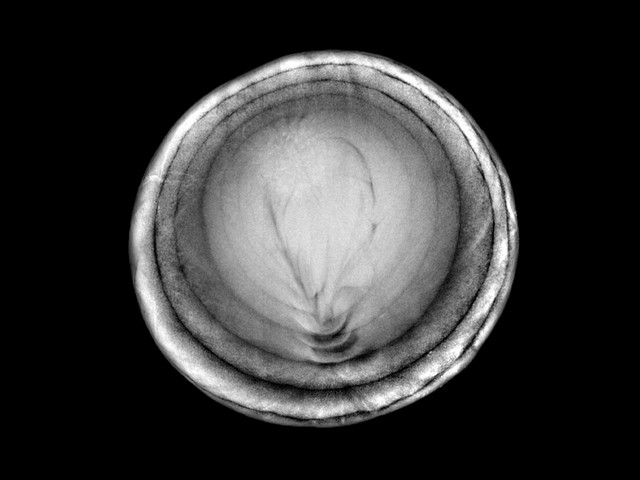

GE, Wilhelm Röntgen’in X ışınlarını keşfettiği gün olan 8 Kasım Uluslararası Radyoloji Günü’nü (IDoR), SeeInsideIT adlı bir kampanya ile kutladı.

Plastik ördekten, arı kovanına; elektro gitardan eski oyun konsoluna kadar dikkat çekici 50’den fazla nesneye ait radyolojik görüntülerin tüm dünya ile paylaşılacağı kampanya ile günümüzde radyolojinin sağlık hizmetlerinde sahip olduğu rolün öneminin ortaya konulması hedefleniyor.

Bilgisayarlı Tomografi – CT , Manyetik Rezonans – MR